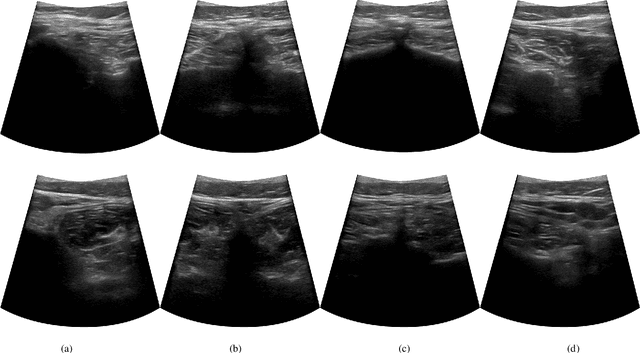

Abstract:Ultrasound (US) imaging is widely used in diagnosing and staging abdominal diseases due to its lack of non-ionizing radiation and prevalent availability. However, significant inter-operator variability and inconsistent image acquisition hinder the widespread adoption of extensive screening programs. Robotic ultrasound systems have emerged as a promising solution, offering standardized acquisition protocols and the possibility of automated acquisition. Additionally, these systems enable access to 3D data via robotic tracking, enhancing volumetric reconstruction for improved ultrasound interpretation and precise disease diagnosis. However, the interpretability of 3D US reconstruction of abdominal images can be affected by the patient's breathing motion. This study introduces a method to compensate for breathing motion in 3D US compounding by leveraging implicit neural representations. Our approach employs a robotic ultrasound system for automated screenings. To demonstrate the method's effectiveness, we evaluate our proposed method for the diagnosis and monitoring of abdominal aorta aneurysms as a representative use case. Our experiments demonstrate that our proposed pipeline facilitates robust automated robotic acquisition, mitigating artifacts from breathing motion, and yields smoother 3D reconstructions for enhanced screening and medical diagnosis.